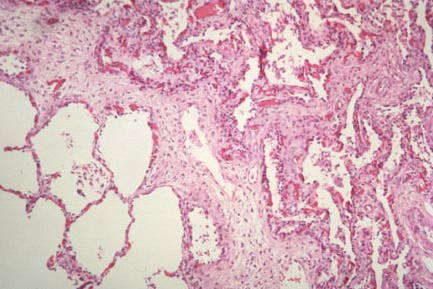

Low power of lung with BPD; severe fibrosis at upper left, compensatory emphysema of less damaged area at bottom right.